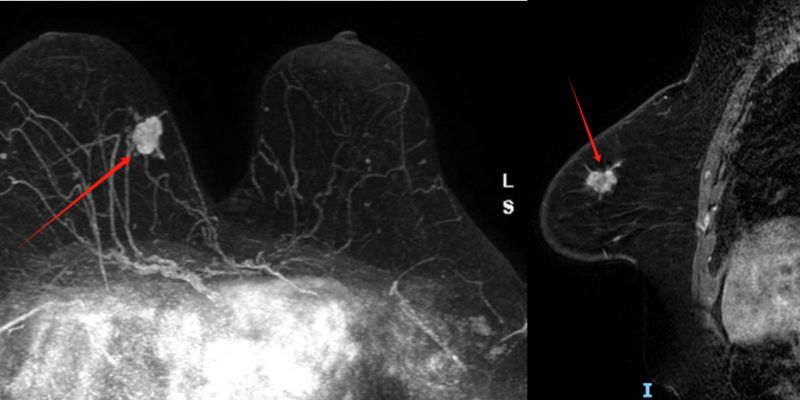

一项针对三阴性乳腺癌(TNBC)的突破性研究,揭示了新的分子亚型和关键的免疫细胞差异(B-细胞),为开发高度个性化的精准免疫疗法奠定了基础,并强调了社会经济因素而非种族生物学差异是导致生存率差距的主要原因。 Read More... "三阴性乳腺癌(TNBC)治疗新突破:揭示免疫差异,精准免疫疗法迎来新希望"

TAILORx和RxPONDER试验彻底改变了HR阳性、HER2阴性早期乳腺癌的辅助化疗决策。本文基于NCDB数据,深度解析21基因表达谱(Oncotype DX)复发评分如何指导淋巴结阴性/阳性患者的化疗选择,帮助患者理解最新的治疗标准和复发风险评估。 Read More... "HR阳性HER2阴性乳腺癌辅助化疗新标准:Oncotype DX复发评分与最新用药指导"